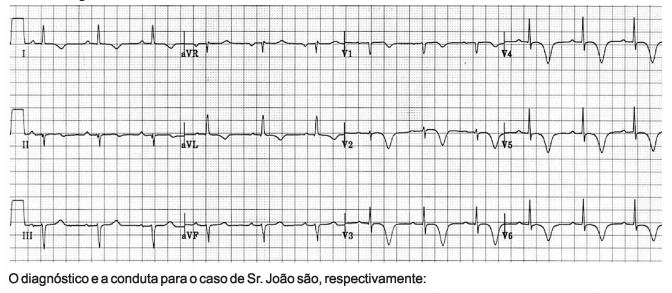

Sr. João, de 51 anos de idade, portador de hipertensão arterial sistêmica, Diabetes mellitus tipo 2 com uso de

insulina, dislipidemia e tabagista ativo com carga tabágica de 45 maços/ano, dá entrada no pronto-socorro. Sua

queixa principal é de dortorácica opressiva, precordial, iniciada após carregar pesos na obra em que trabalha há

cerca de 45 minutos, que foi seguida de dispnéia intensa. Ao exame físico, sua PA é de 84 x 52 mmHg, sua

frequência cardíaca de 68 batimentos por minuto, S p02 de 86% em ar ambiente e sua frequência respiratória de

37 incursões por minuto. Encontra-se obnubilado, com extremidades frias, sudoreico e com fala escandida e

entrecortada. A ausculta pulmonar revela crepitações bolhosas bilateralm ente até os ápices. Seu

eletrocardiograma revela:

Provas